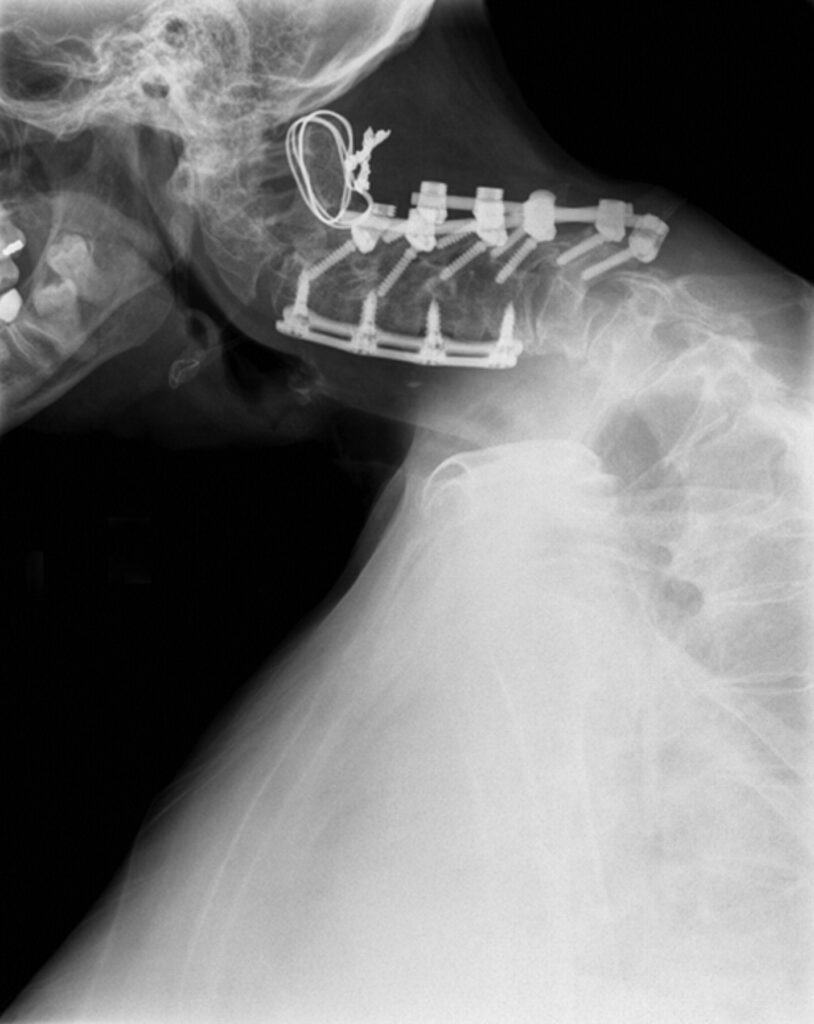

D. Kirurgjia

Rrallë aplikohet, vetëm në raste të:

• deformimit të përhershëm cervikal

• spondilozës së rëndë

• paaftësisë totale për të mbajtur kokën